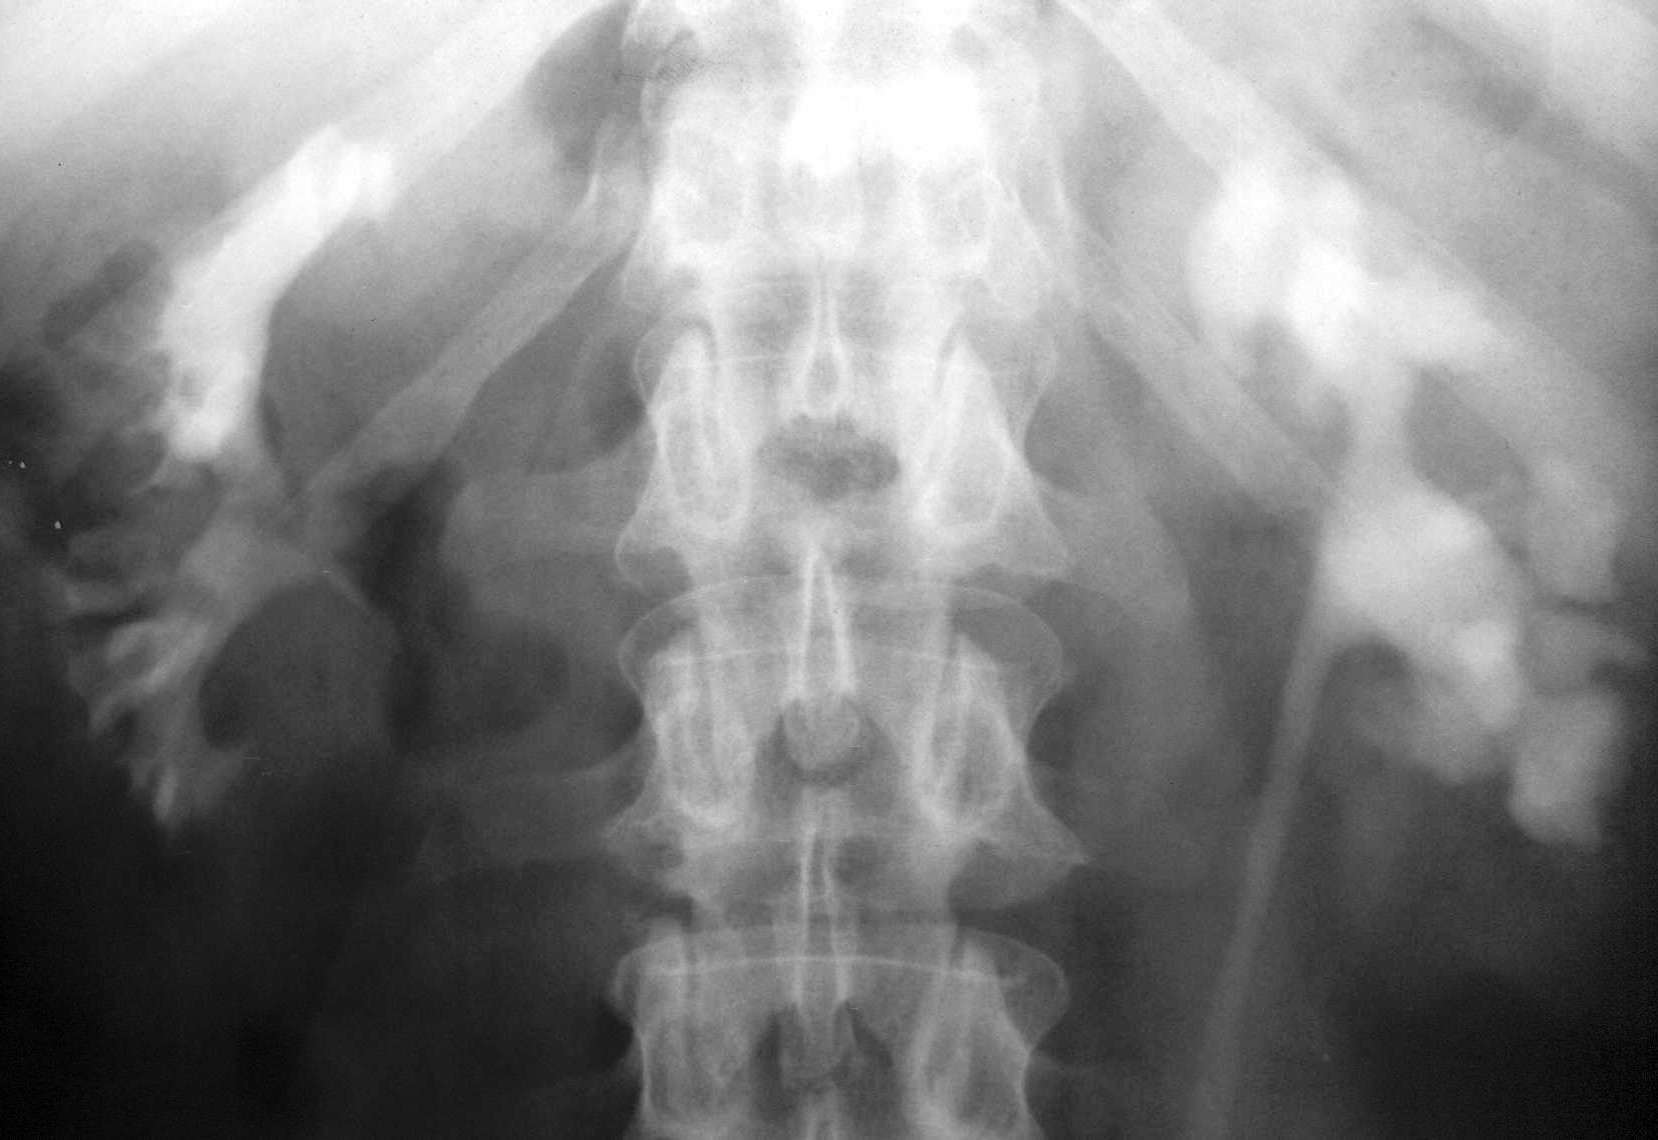

- Figure 4: IVP showing papillary necrosis

- Figure 5: Retrograde pyelogram showing multiple cavities in the right kidney caused by TB caseous necrosis